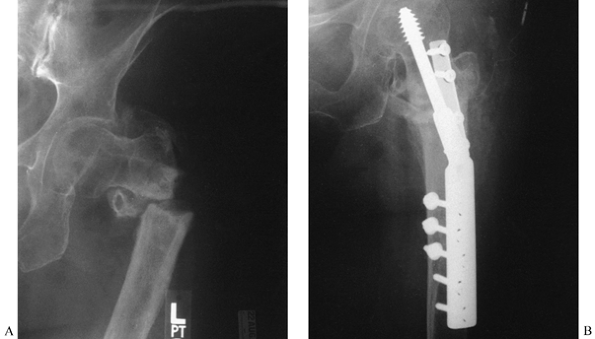

Figure 29.10. A:

A 55-year-old woman 3 years after an intertrochanteric fracture of the

left hip. She was originally treated with a Smith-Peterson nail and

Thorton side plate. This was complicated by infection with a

penicillin-sensitive Staphylococcus aureus. Now she has painful nonunion with 1½-inch (3.75 cm) shortening. B:

This was treated with reduction, autologous bone graft, and double

plate fixation with a hip screw and semitubular plate. She healed and

regained her lost leg length and function. -